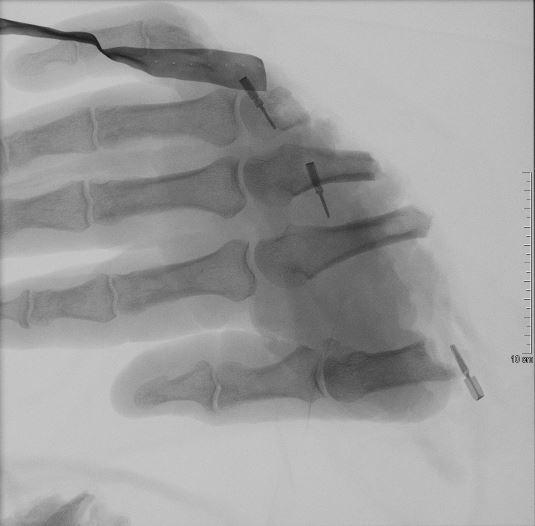

Nach der Aufnahme des Verletzten über den Schockraum mit einer ersten Sichtung der abgetrennten Hand, schloss sich umgehend die operative Versorgung an: Durch eine neunstündige Notfalloperation konnte die Hand erfolgreich wieder angesetzt werden. Hierzu sind spezielle Voraussetzungen erforderlich. Neben dem Vorhandensein eines Operationsmikroskops, welches das OP-Gebiet um ein Vielfaches vergrößern kann, sind mikrochirurgische Erfahrungen des Operateurs wesentlich. Zunächst wird die abgetrennte Gliedmaße im Bereich der Knochen mit einfachen, schnellen Methoden während der „Damage Control Surgery“ mit dem Körper verbunden. Dann schließen sich längere Zeiträume unter dem Operationsmikroskop an, um schnellstmöglich zuerst die durchtrennten Arterien wieder zu vereinigen, damit die Durchblutung der abgetrennten Gliedmaße wiederhergestellt ist. Der Zeitraum zwischen Unfall bis zur Wiederherstellung der Durchblutung sollte sechs Stunden nicht überschreiten. Anschließend werden die Sehnen und Nerven sowie abschließend die Venen genäht. Dieser letzte Operationsschritt mit Naht der Venen ist mit einer der wichtigsten Schritte der gesamten Operation. Neben einem Bluteinstrom muss auch immer der Blutausstrom gewährleistet sein, da es ansonsten trotz perfekten Anschlusses zu einem Absterben des Replantates kommen kann. An eine erfolgreiche Replantation schließt sich dann eine aufwändige Überwachungsphase von etwa einer Woche mit anfänglich stündlichen Kontrollen der abgetrennten Gliedmaße an, um zeitnah bei etwaigen Problemen reagieren zu können. Zusammenfassend lässt sich sagen, dass je stumpfer oder gequetschter die Amputationsstellen sind, sich die Erfolgsaussichten dieser Operation umso schwieriger oder unmöglich gestalten. Im aktuellen Fall lagen günstige Voraussetzungen für eine erfolgreiche Replantation vor, so dass davon auszugehen ist, dass die Hand nach einiger Zeit zumindest wieder eingeschränkt einsetzbar ist.